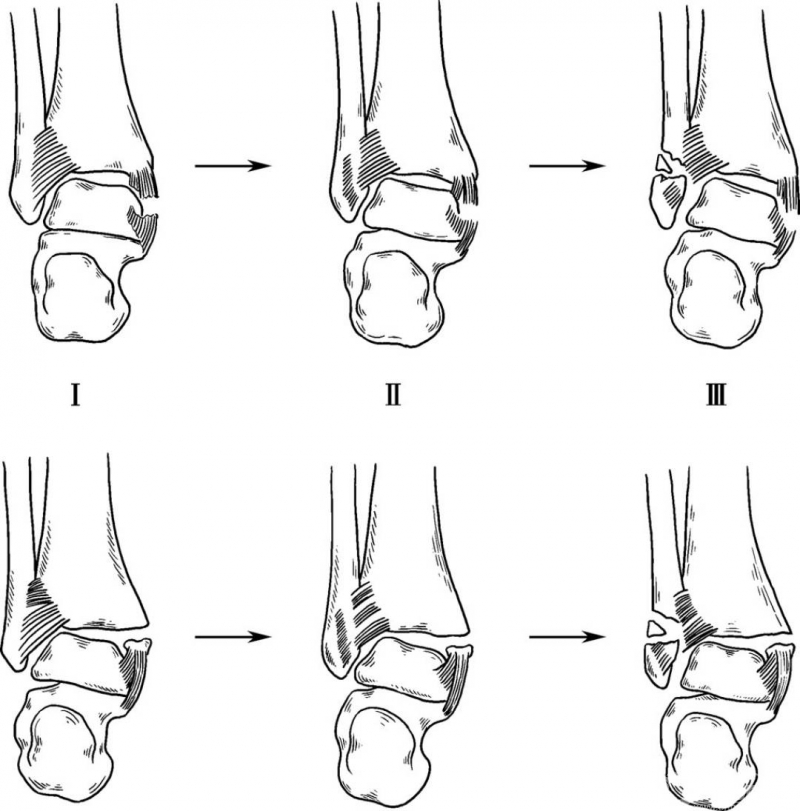

1. 旋后—内收型

旋后是指距下关节内翻、胫距关节内旋和前足内收,此时第一跖骨及足心朝向头侧,第五跖骨向尾侧。此位置时踝外侧结构绷紧,在旋后和内收外力作用下,首先会造成外侧副韧带断裂或发生外踝撕脱骨折、横形骨折。骨折在下胫腓联合韧带下方,下胫腓韧带仍保持完整。进一步的内收距骨撞击关节内侧,结果造成与距骨内角垂直的骨折线,有时会造成胫骨远端内侧关节面压缩,也可能造成距骨软骨下压缩性骨折。旋后—内收型骨折分两度(图1)。

图1 旋后—内收型